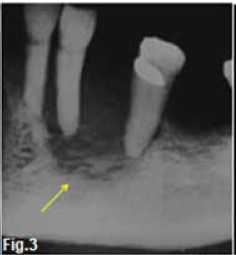

The cropped pantomograph (Fig. 1) shows marginal resorption of the alveolar crests while Figure 2 shows a nonspecific area of rarefaction in the canine-premolar region (red arrow) without evidence of sclerosis at the margins of the lesion. Figures 3 & 4 are radiographs of the resected specimen showing the changes more clearly. Permeative changes, lack of marginal sclerosis (yellow arrow) and absence of periosteal reaction indicate a malignant process but do not confirm a specific disease. The "geographic area" results from total destruction of the buccal half of the mandible (blue arrow). A histological examination confirmed the diagnosis of a primary intraosseous carcinoma.